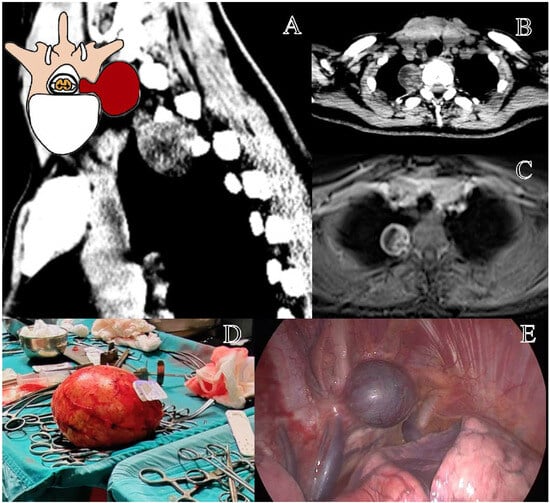

The Eden class II lesions are rarer and less studied in the literature [3]. There is a lack of evidence regarding their optimal management [3,8]. Due to the rarity of the pathology, these tumors are often investigated together with the cervical and lumbar ones, preventing the drafting of reliable recommendations [25]. The presence of sacrificable thoracic nerve roots and the complex anatomy of the posterior mediastinum justify considering these lesions as a distinct entity [7]. In our opinion, the perception of spinal instability in these lesions warrants further investigation [26]. In our study, bilateral LCT and TPD were the investigated approaches. TPD presumably required significantly longer surgical times to create larger surgical corridors [19,29], yet did not result in substantially higher GTR rates compared to LCT (100% vs. 88%). This aspect remains an open question. Further well-structured and focused studies are needed to determine the most appropriate surgical approach for these rare Eden class II lesions. Furthermore, the resection of the ipsilateral pedicle and articular facet would presumably raise concerns regarding thoracic spinal instability (Figure 2) [19,29]. Therefore, while our study describes the enrolled cases, it does not allow us to definitively advocate the best surgical approach for these lesions. The need for secondary stabilization has been explored in studies on thoracic disk herniations [19,27]; however, these findings may not be directly applicable to intradural tumors [16].

Figure 2. Representation of a T5–T6 schwannoma, Eden Type II. (A) Preoperative sagittal T1-weighted MRI with contrast, showing a lesion at the right T5–T6 level with both intradural-extramedullary and foraminal extension. (B) Axial MRI demonstrating the extradural and foraminal components of the lesion, with wide erosion and remodeling of the bone vertebral structure. (C) Intraoperative view following a laminectomy, exposing the tumor. (D) The transpedicular exposition of a tumor, with the demolition of the ipsilateral pedicle and articular facet.